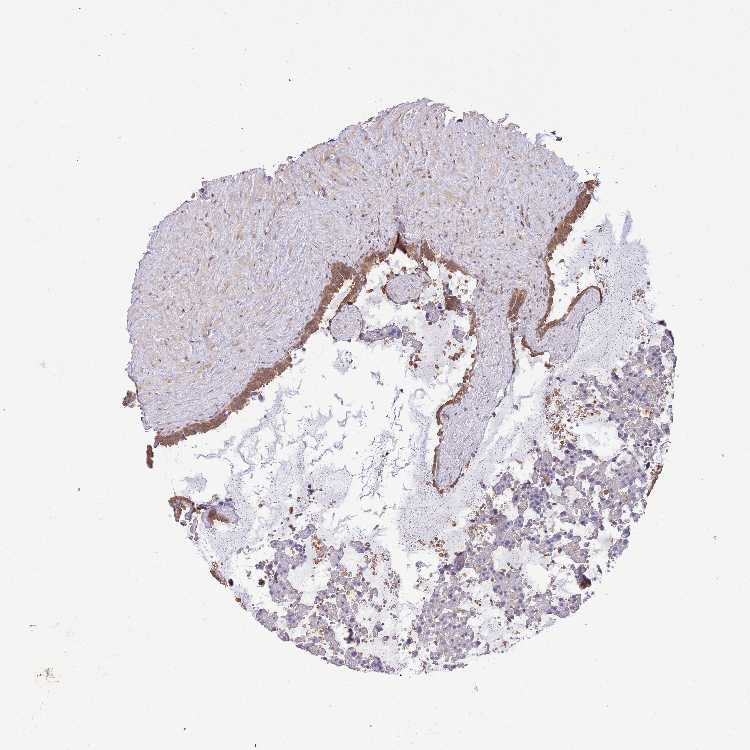

SEMINAL VESICLE - Antibody stainingi

Antibody staining in the annotated cell types in the current human tissue is reported as not detected, low, medium, or high, based on conventional immunohistochemistry profiling in selected tissues. This score is based on the combination of the staining intensity and fraction of stained cells.

Each image is clickable and will lead to virtual microscopy that enables deeper exploration of all samples and also displays staining intensity scores, fraction scores and subcellular localization as well as patient and tissue information for each sample.

Antibody HPA046152

Glandular cells Medium